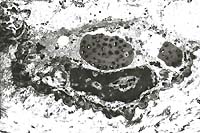

- Case 24-1. Low power view has necrosis and inflammation

of nasal mucosa and thrombosis of nasal vessels. Larger thrombus

demonstrates lines of Zahn (layers of fibrin, wbcs, platelets,

RBCs, etc). Higher power view of vessel wall infiltrated and

replaced by mostly degenerate neutrophils and fibrin. Lines of

Zahn are seen more clearly on the left.